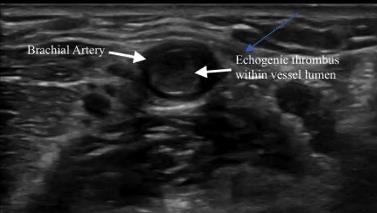

302 Acute Brachial Artery Occlusion on Point-of-Care Ultrasound in the Emergency Department: A Case Report

AY Mughal, P Kishi

calculate bicarbonate and base excess due to a pH more than 7.70. The patient underwent an abdominal ultrasound in the ED, which suggested IHPS with an enlarged pyloric channel measuring 2.1 cm and a thickened muscle measuring 0.5 cm, again with minimal passage of fluids through the pylorus (Image 1). The surgical team was consulted for the abnormal laboratory and ultrasound findings, but due to the possibility of postoperative edema or residual abnormal external pylorus measurements, the consultant recommended further imaging to conclusively determine pyloric stenosis. The child was admitted for fluid resuscitation and electrolyte replacement. An upper GI series performed the same day confirmed the diagnosis of IHPS when there was lack of contrast passing from the stomach to the duodenum. The patient received a solution of intravenous 5%, dextrose, half normal saline, and 40 mEq potassium chloride at maintenance until electrolytes and intravascular volume